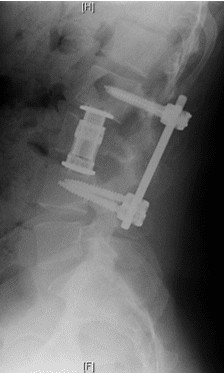

Surgery

Patient was operated and the spinal canal cleaned up of all bony fragments. The spine was fixed from the side and the back to take care of instability.